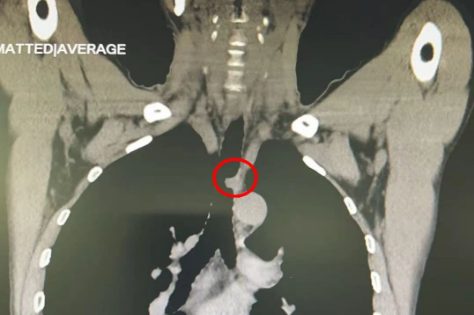

春节刚过,北京天坛医院胸外科主任魏博就在门诊看见了杜先生。由于反复咳嗽,杜先生到老家医院求医,发现气管腔内有肿物,并确诊为气管腺样囊性癌,“找了三家医院,都说做不了这个手术,后来在网上看到天坛医院胸外科有这方面的专家,就赶紧过来了”。“这种肿瘤发病率很低,由于气管的特殊结构,手术难度也比较大。”但杜先生的CT显示,他的气道已经被肿瘤堵塞了一大半,如果再发展下去,有可能危及到他的生命,魏博拍板,马上把杜先生收治入院。

第一关顺利通过,紧接着就是第二关:气管切除与重建。气管长度只有10-12厘米,切得范围太大,上下两段的气管可能会出现“对不上”的局面,而切得小了,则可能不能完全切除肿瘤。在气管镜的帮助下,手术团队精准地找到肿瘤的边缘,顺利切断肿瘤的下级。